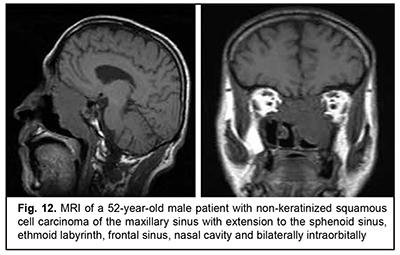

Keratinized squamous cell carcinoma and non-keratinized squamous cell carcinoma are similar in their course and grow locally. Their intracranial growth is mild (Figs 11, 12). Adenoid cystic carcinoma is a highly differentiated cancer that commonly grows locally at the site of origin. The tumors grow expansively (Fig. 13), and may extend intracranially and intracerebrally. Adenocarcinomas are malignant tumors of the lacrimal and salivary glands and paranasal sinuses characterized by early intracerebral invasion with an aggressive course. Fig. 14 shows the adenocarcinoma of the ethmoid labyrinth with significant intracerebral growth and perifocal edema, involvement of the falx, and extension along the anterior falx to skull base and orbit bones with invasion and destruction of these bones.